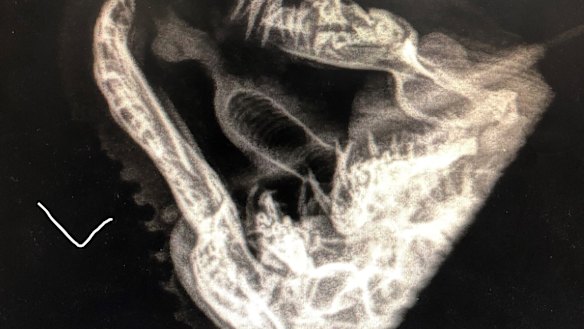

An X-ray of the snake's jaw that showed significant trauma.

"After doing some X-rays under anaesthetic, we saw she suffered significant trauma and had broken her jaw in multiple places but nobody knows when or how it happened.

"So when her teeth healed, they grew back abnormally.

"Instead of sticking up straight, her teeth were poking in her mouth so it was no wonder why she wasn't eating."